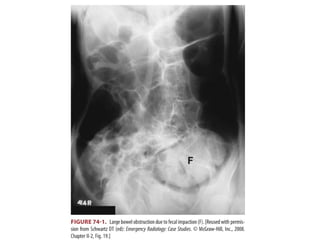

• If fecal impaction is the cause, manual disimpaction

is the treatment.

ORGANIC CONSTIPATION • Symptomssuggestive of organic constipation are acute onset, weight loss, rectal bleeding/melena, nausea/vomiting, fever, rectal pain, and change in stool caliber • Intestinal obstruction or carcinoma is the primary consideration. • If fecal impaction is the cause, manual disimpaction is the treatment.